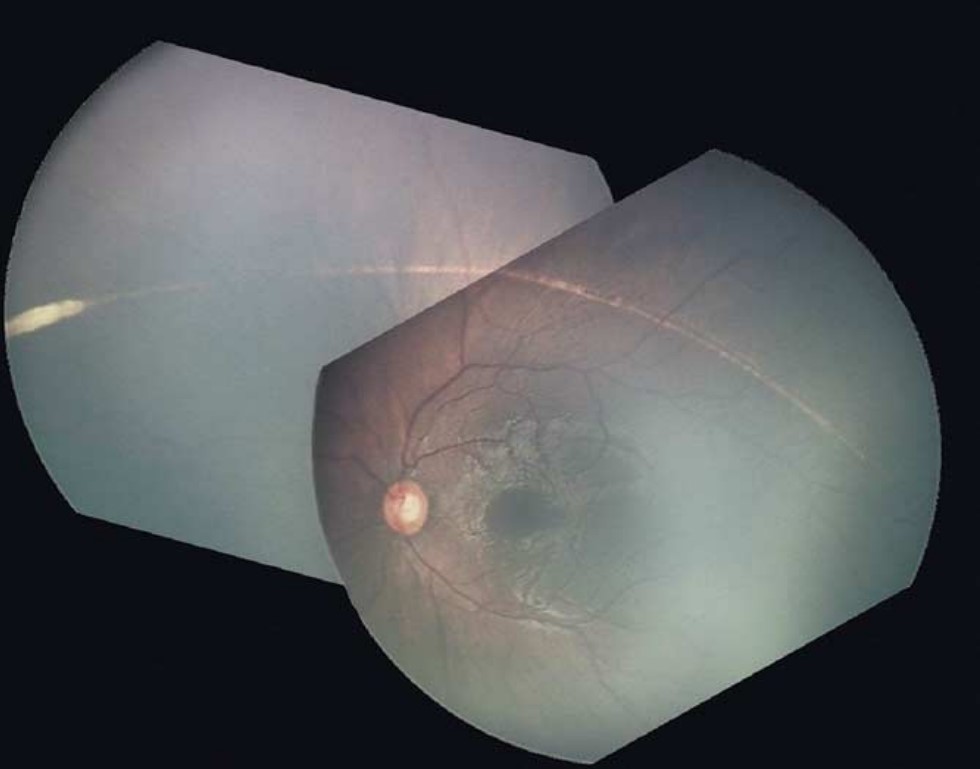

- 녹내장 약물을 투여해도 각막 혼탁이나 각막 부종이 빠지지 않아 전방각의 관찰이 불가능한 경우

술전에 약물 치료를 통해서 최대한 각막부종이나 각막 혼탁을 줄여주어야

수술당시 시야확보에 도움이 되기 때문에, 약물 치료를 시행합니다.

공막절편을 들어올린 상태에서 윤부에서부터 1mm정도 정도에서 절개를 해나가면,

푸르스름한 조직에 Schlemn canal 이 관찰됩니다.

쉴렘관의 외벽을 절개하는 순간 소량의 출혈이 있거나, 방수가 스며나오는 것을 통해서

쉴렘관의 위치를 알수 있습니다.